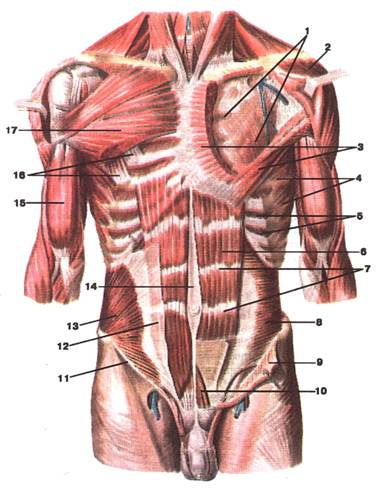

Малюнок А. 2 – М'язи тулуба (грудей та живота). Вигляд спереду:

1 -lamina profunda fasciae pectoralis; 2 -m. deltoideus (відтягнутий вбік); 3 -m. pectoralis major (частково видалений); 4 -m. serratus anterior; 5 -mm. intercostales interni; 6 -m. rectus abdominis; 7 -intersections tendineae; 8 -m. transversus abdominis; 9 -m. obliquus internus abdominis (відрізаний та відвернутий); 10 -m. pyramidalis; 11 ‑lig. inguinale; 12 -aponeurosis m. obliqui interni abdominis; 13 -m. obliquus internus abdominis; 14 -linea alba (abdominis); 15 -m. biceps brachii; 16 -m. pectoralis minor; 17 -m. pectoralis major